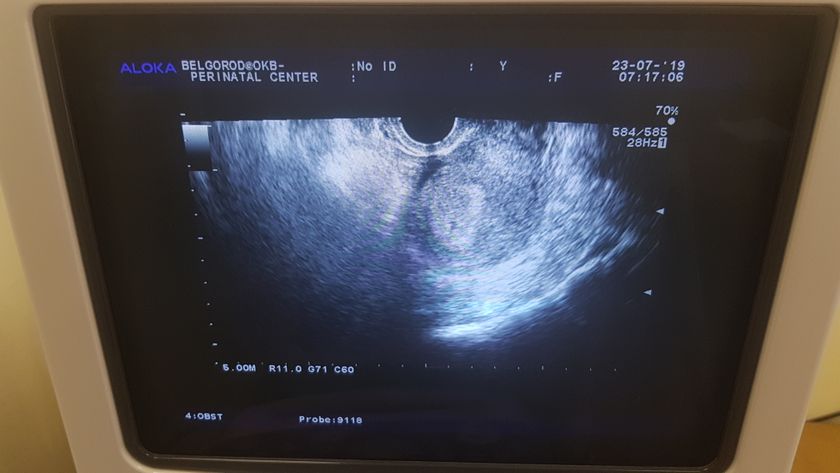

Приветик, девочки)) я так ждала этого малыша и вот заветные полосочки)) Это третья беременномть, но все иначе. Сильно болят соски, ноет низ живота и слабость)) начал появляться животик и вес на кг уже. Принимаю фолиевую, дюфастон и магнелис)